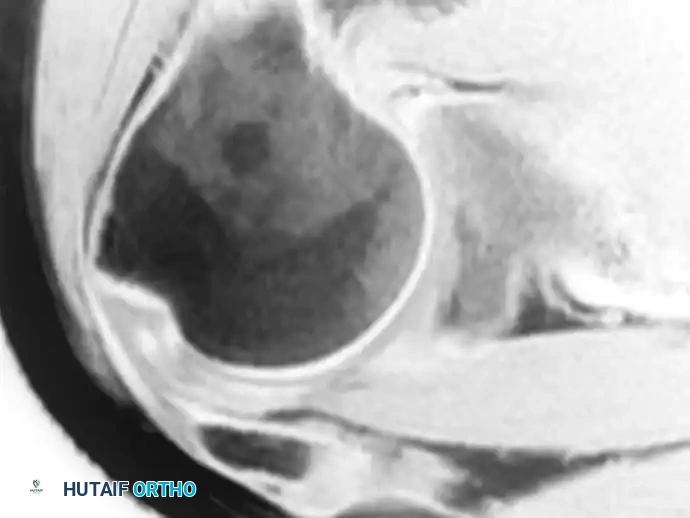

Osteoclastoma of Humeral Head

-

Pathology (10): The humeral head has been replaced by a huge mass of poorly differentiated bone.

Diagnosis: the appearances are typical of osteoclastoma (giant cell tumour of bone), a locally malignant condition which may, however, on occasion become invasive and metastasise.